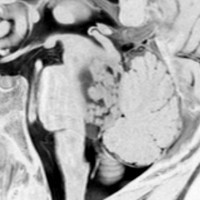

小児の神経節細胞腫 gangliocytoma グレード1(過誤腫のような良性腫瘍)

10才の時に,複雑部分発作(症候性てんかん)で発症しました。吐き気を感じた後に嘔吐して意識が遠くなる(意識減損)という症状であり,側頭葉てんかんです。脳波では左側頭葉に徐波律動がみられました。発作は頻回でしたがカルバマゼピンの投与で抑制されていましたが,MRIで腫瘍が発見されました。

左内側側頭葉グリオーマ mesial temporal glioma と呼ばれる腫瘍です。左の扁桃体,海馬鉤,海馬,海馬傍回に腫瘍が浸潤しています。T2強調画像とFLAIRでまだらな高信号で境界ははっきりしません。mass effectが少なく,増殖増大傾向のある腫瘍には見えないのが特徴です。下段右のように部分的にガドリニウム増強されるのも神経節細胞腫の特徴かもしれません。しかし,神経節膠腫,乏突起膠腫,乏突起星細胞腫(グレード2)なども疑われます。

手術中の脳波モニターでは,棘波が上側頭回の後方(ウェルニッケ領域)に存在し,深部電極刺入で海馬近傍にも棘波がみられましたが,もちろん上側頭回や海馬の切除はしませんでした。扁桃体 amygdala と海馬鈎 uncus の腫瘍部分のみを切除して手術を終了しています。海馬と海馬傍回には腫瘍を残しました。上のMRIは,その後6年経過した後のものですが腫瘍は全く同じ大きさです。抗てんかん薬も止めて,発作は全く生じていません。このような腫瘍は,扁桃体と海馬鉤を摘出することで,発作を完全に止めることができることがあります。ですから,最初の手術では,リスクのある余分な脳切除をしません。

大脳皮質に大型の核を有する円形の神経細胞が散在しています。神経細胞間にグリア細胞がありますが腫瘍性増殖を示しません。MIB-1は1%以下でした。血管周囲にリンパ球浸潤があります。